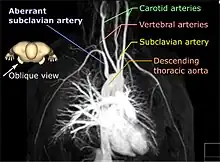

| Aberrant subclavian artery on MR angiography. | |